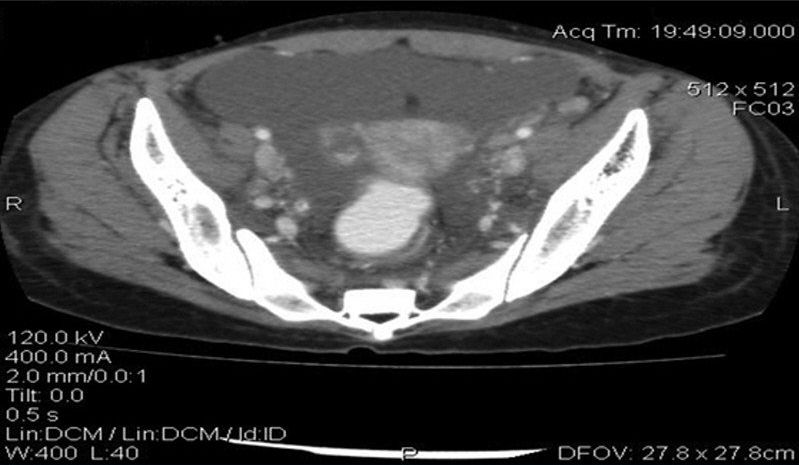

癌胚抗原(CEA)水平正常,但CA-125水平升高为93.5μg/ml(正常范围,0~35μg/ml)。进行腹部和盆腔的CT扫描,证实存在中度腹水和腹膜结节(图2)。膀胱壁和肠壁增厚(图3)。双侧肾积水和多个扩大的主动脉旁淋巴结也可见(图4)。

图2 盆腔增强CT显示盆腔游离液体

图3 腹部增强CT显示肠袢增厚